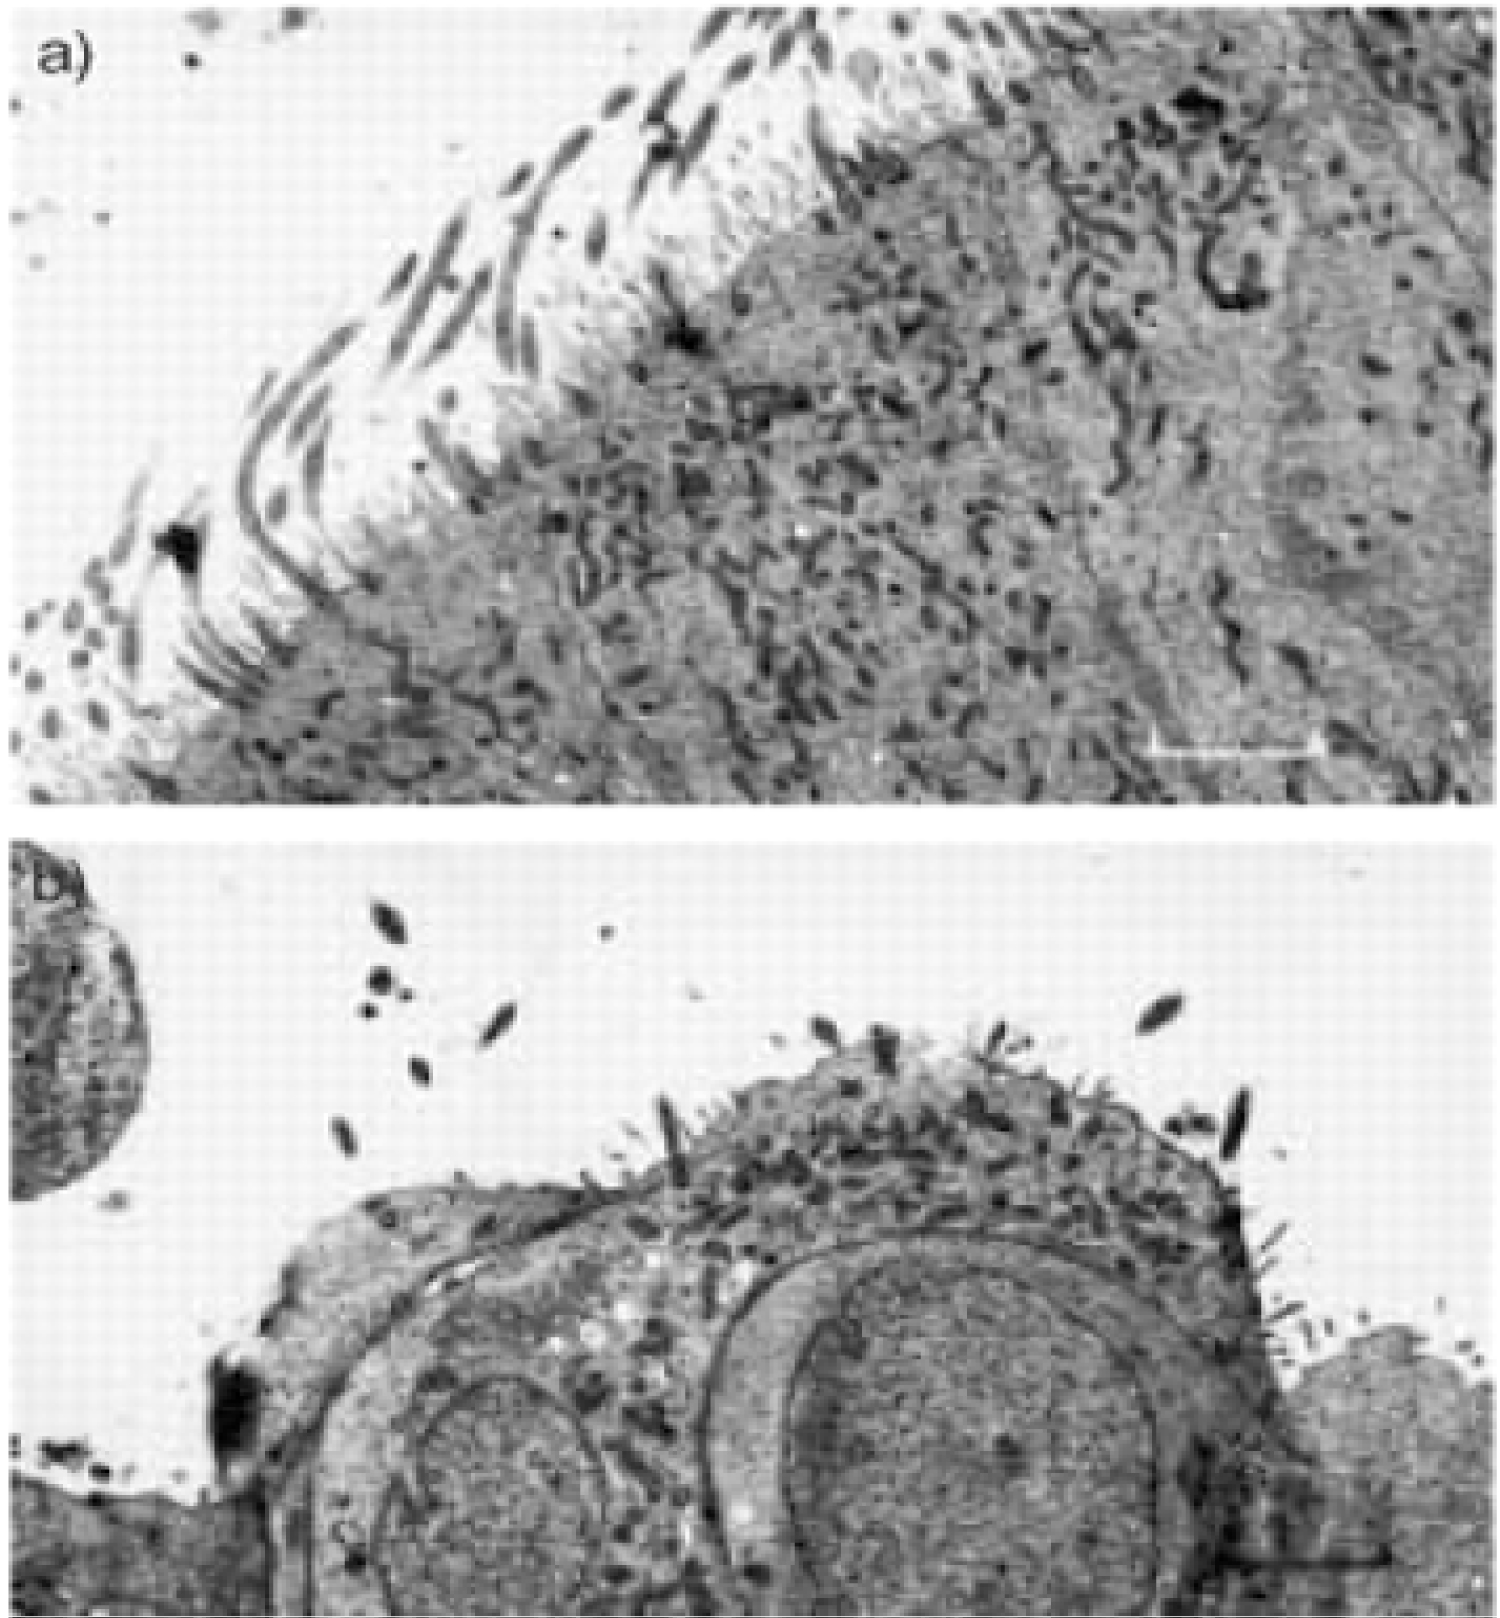

As a result, SARS-CoV-2 can bind 10 times more tightly to insert its RNA into the cell, starting to explain why COVID-19 spreads so rapidly [25,26] (Figure 5).

Figure 5: Transmission electron micrograph of nasal epithelium before and after coronavirus inoculation. a) Transmission electron micrograph day 0. This shows normal tissue with an intact well-ciliated surface and minimal disruption; b) Transmission electron micrograph day 3. This shows abnormal tissue with severely disrupted cell surface. Marked loss of cilia is seen. Internal scale bars = 2.9 µm [26]. View Figure 5